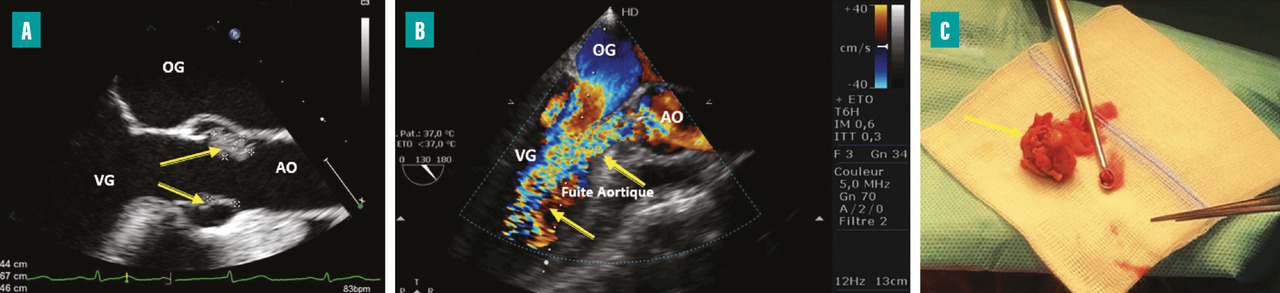

L’insuffisance cardiaque est la complication la plus fréquente (50 à 60 %) et la première cause de mortalité dans l’EI.3Un délabrement valvulaire important peut entraîner une fuite valvulaire sévère (

La surveillance de l’apparition ou de l’aggravation de signes d’insuffisance cardiaque au cours de l’évolution de l’EI est primordiale. L’auscultation cardiopulmonaire quotidienne fait partie des éléments clés de la surveillance. Les échographies transthoracique (ETT) et transœsophagienne (ETO) restent les examens de référence pour le diagnostic et la surveillance de l’évolution des lésions valvulaires.2

La recherche de signes de mauvaise tolérance échographique de la fuite (élévation de la pression télédiastolique du ventricule gauche, hypertension artérielle pulmonaire…) doit amener à discuter la chirurgie même si l’insuffisance cardiaque est cliniquement bien tolérée ou stable. Les indications opératoires pour insuffisance cardiaque sont discutées au sein de l’équipe pluridisciplinaire qui doit sélectionner les patients à opérer et planifier cette chirurgie en prenant également en compte les risques liés à l’intervention.4